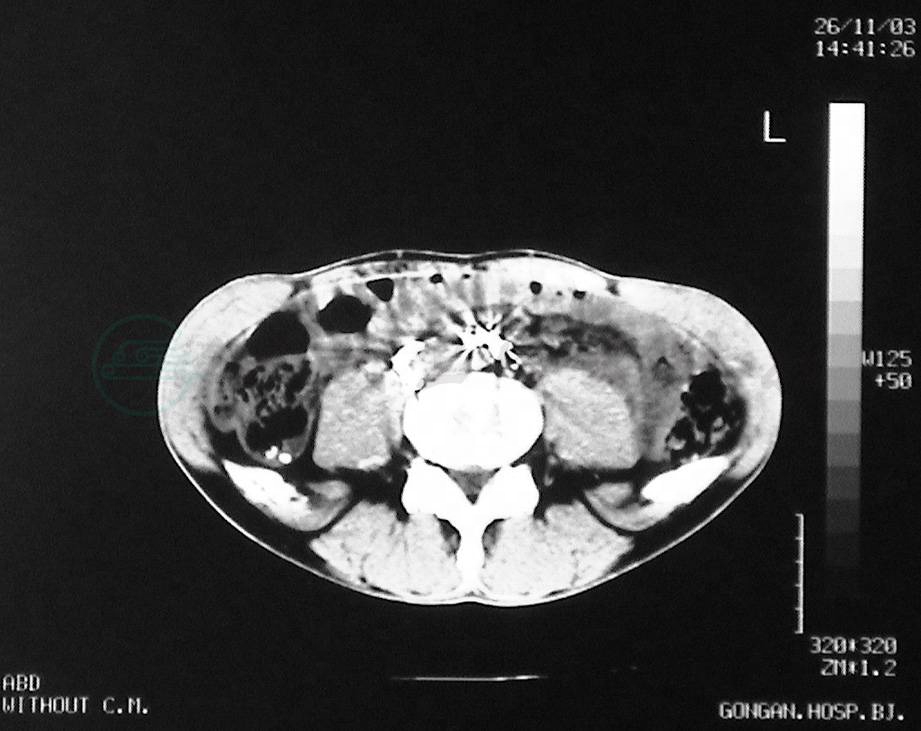

5.直接淋巴管造影后的CT影像

对淋巴管疾病直接淋巴管造影后的患者,选择性做CT检查(简称淋巴管增强CT,lymphatic contrast computed tomography,LCT)以进一步探讨淋巴管疾病的诊断、认识淋巴管疾病的病理生理过程。

普通CT影像对淋巴管结构难以有阳性发现。LCT影像,能精细地显示造影剂分布状况,清楚地显示造影剂与周围脏器的关系,在直接淋巴管造影基础上,能更全面地了解淋巴管病变范围与准确部位,能发现淋巴管造影的资料遗漏,对乳糜回流障碍的诊断,以及对手术方式的选择,尤其是对要结扎的淋巴管或要切除肿物的准确定位,有重要作用,还能发现骨骼淋巴管病变、碘油进入骨骼结构等。因此,在直接淋巴管造影不能做出判断时,可选择行LCT检查。但因其影像是平面的,不能准确提供造影剂与周围组织脏器的关系,因人为选择摄片区域和时间,可能造成影像资料无意丢失。